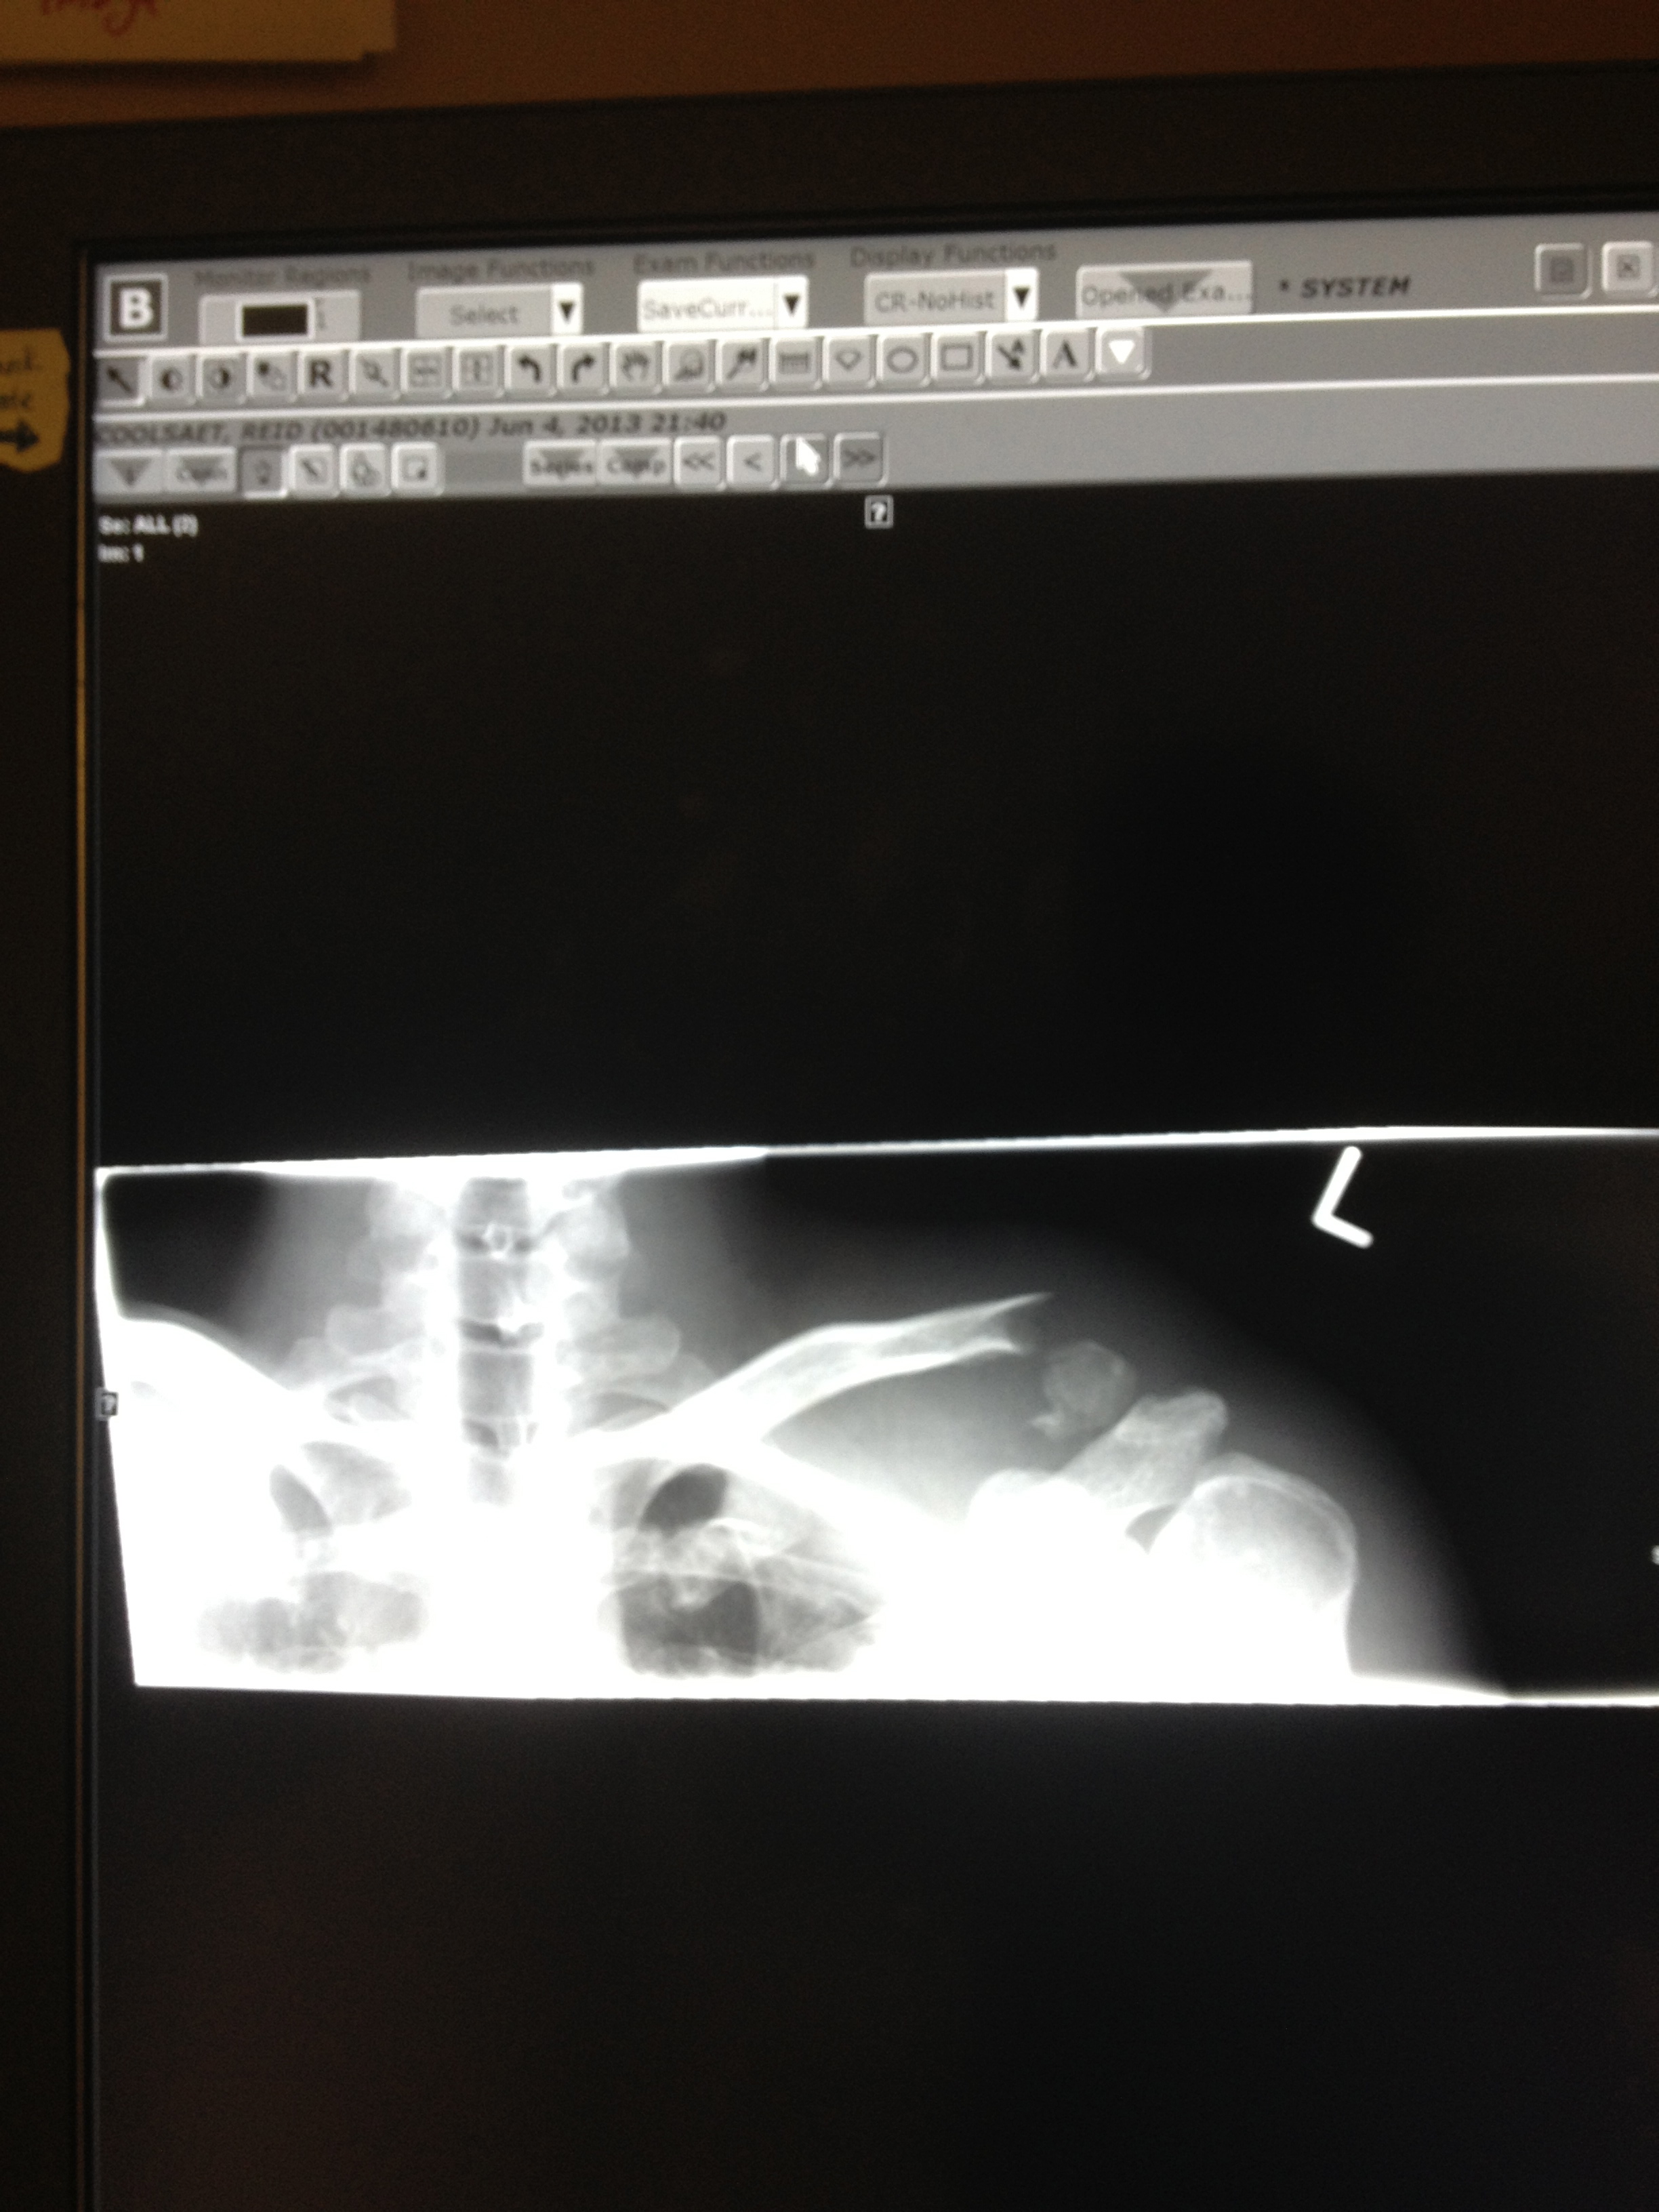

here you can see the shoulder on the right, my left shoulder, has a break.

Dave, Moulton and Deb met me at the hospital. Moulton broke his collar bone last year and had some useful tips for flossing teeth, getting on shirts… i finally got in for some x-rays and right when i saw them thought ‘how the hell is that supposed to join back together.’

i am scheduled to see an orthopaedic surgeon tomorrow as this particular fracture often requires surgery. there is a chance of nonunion with such a gap.